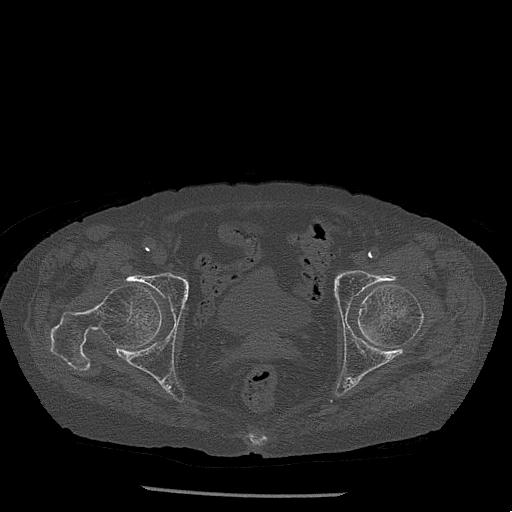

100703 1/27 両股正面+軸 1/29 両股正面+軸 94歳女性 パンソンロン